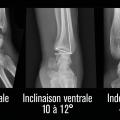

La surface articulaire distale, encroûtée de cartilage, répond au carpe distalement et présente deux facettes, scaphoïdienne et lunarienne (fig. 3), séparées par une crête de direction antéropostérieure. Cette surface articulaire a une double concavité transversale et sagittale. Il est crucial de retenir qu’elle possède une double inclinaison ventrale (10 à 12° en moyenne dans le plan sagittal) et médiale (22 à 24° en moyenne dans le plan coronal), très spécifique, qu’il faudra s’efforcer de restituer et de maintenir dans le traitement de la composante métaphysaire de ces fractures (fig. 4). L’index radio-ulnaire distal, défini par la longueur relative du radius par rapport à l’ulna, est le troisième critère morphologique à évaluer (fig. 4). Ce dernier, dont les valeurs normales sont très variables, est en moyenne neutre à 0 mm (-3 mm à +2 mm).